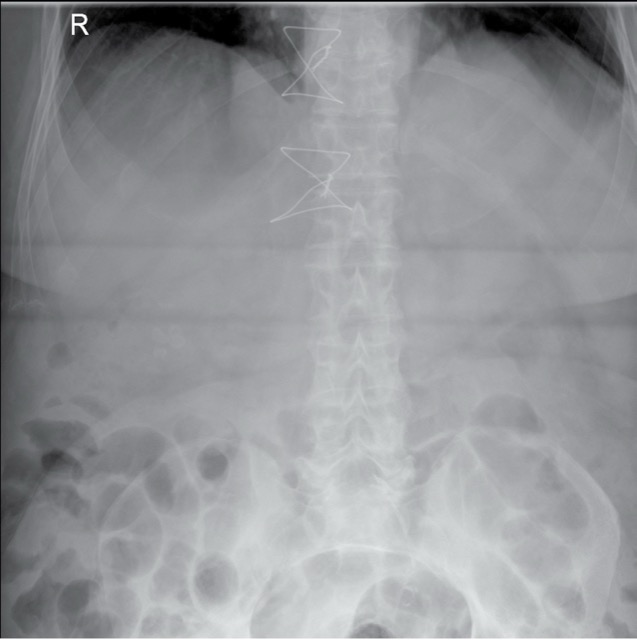

Orthopaedic

4 pattern guides